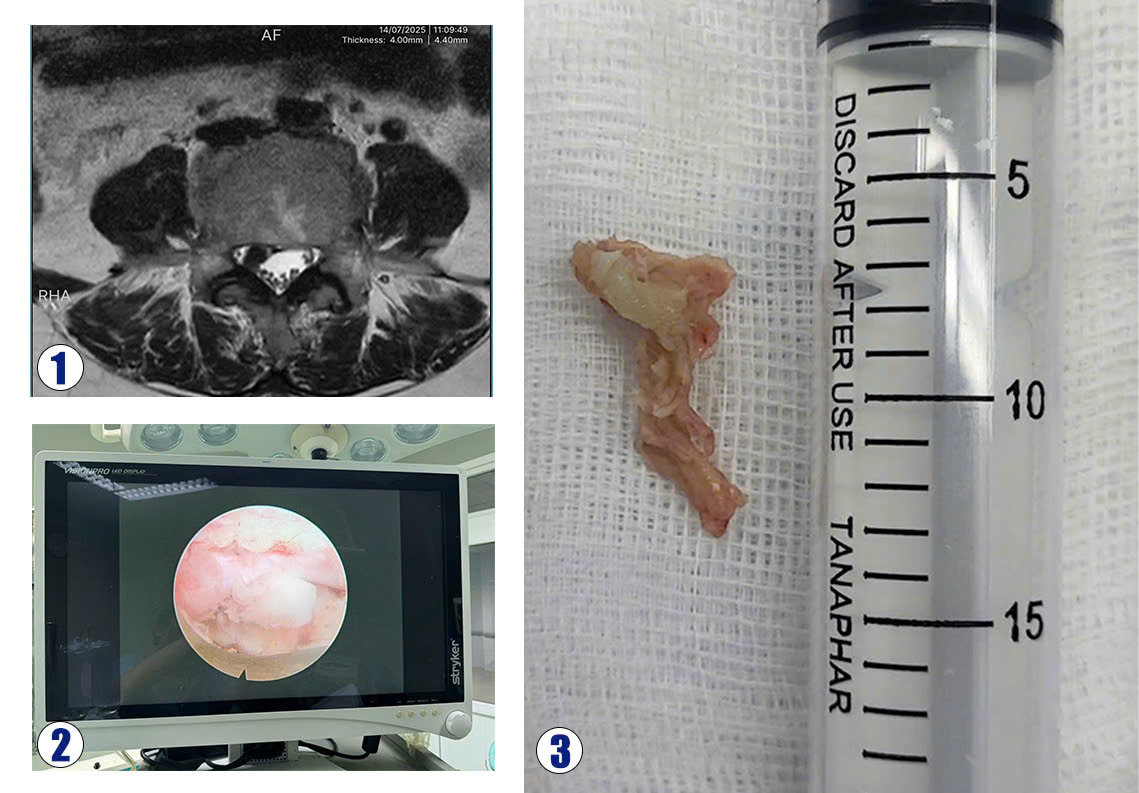

Hình ảnh (1) Khối thoát vị trên phim MRI, (2): Khối thoát vị qua nội soi, (3): Khối thoát vị khi lấy ra

Bệnh nhân Nguyễn Thị S., 53 tuổi, ở xã Nghĩa Đàn – Nghệ An nhập viện trong tình trạng đau dữ dội chân phải, đi lại khó khăn. Bệnh nhân đã được điều trị nội khoa 2 tuần nhưng không đỡ đau. Kết quả chụp MRI cột sống thắt lưng phát hiện khối thoát vị đĩa đệm L4L5 chèn ép rễ L5 bên phải. Bệnh nhân được phẫu thuật nội soi lấy khối thoát vị đĩa đệm. Ca phẫu thuật kéo dài gần một tiếng, khối thoát vị đã được lấy qua nội soi, rễ L5 phải được giải phóng chèn ép. Sau phẫu thuật, bệnh nhân hết đau hoàn toàn chân phải, vận động tốt và trở lại sinh hoạt thường ngày chỉ sau một ngày.